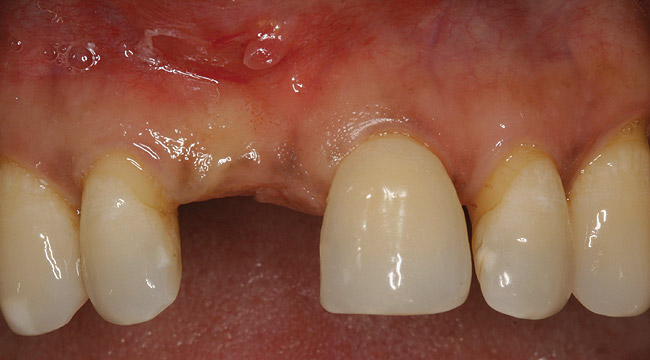

A 45-year-old woman presented with a narrow edentulous ridge in the maxilla (Figure 1). Following adequate anesthesia, a horizontal incision palatal to the crest and two vertical incisions were placed to outline the surgical field. A periodontal probe was used to measure the width of the alveolar crest at the most coronal dimension after a full-thickness flap was elevated (Figure 2). From the author’s experience, it was not necessary to maintain palatal bone-periosteum.

Figure 1  Patient missing maxillary right central incisor presents with ridge deficiency.

Figure 1

Figure 2  Inadequate alveolar thickness of 3 mm in the buccopalatal dimension shown after full-thickness flap reflection.

Figure 2